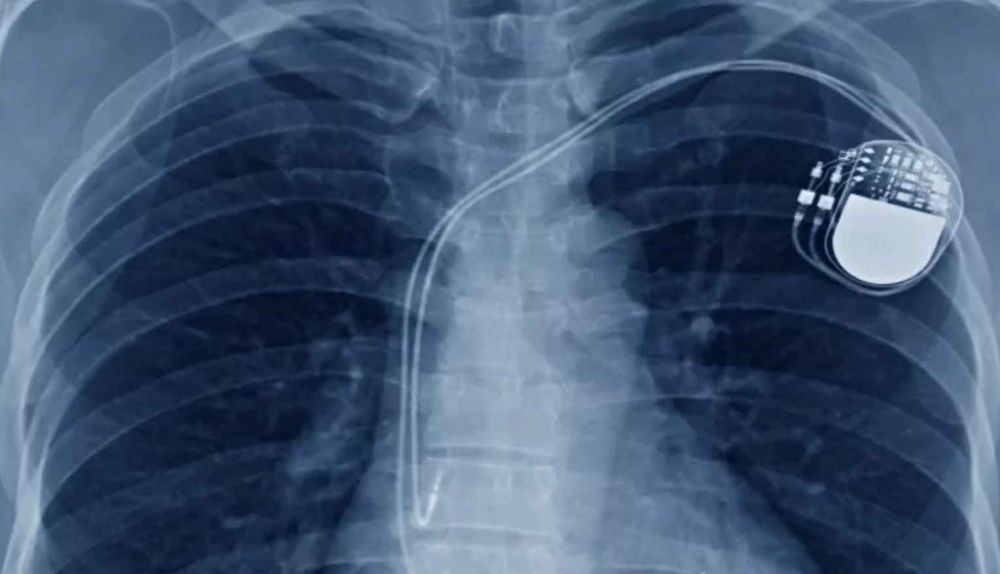

Para solucionar este grave problema de salud, el joven necesita una operación para que le coloquen un DAI (desfibrilador automático implantable), ya que su vida corre peligro. Desde el Hospital de Puerto Real se han puesto en contacto con el de Cádiz, que es el que tiene que dar el consentimiento para solicitar el dispositivo y operarlo.